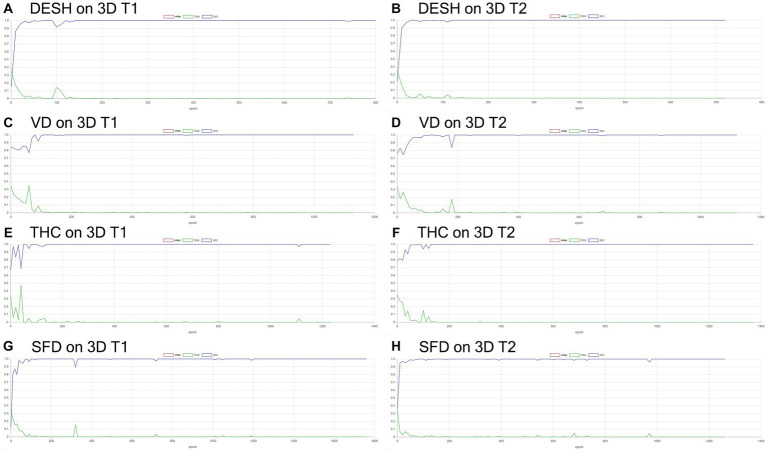

Volumetric semantic segmentation

Training and internal validation of the 3D U-Net model for semantic segmentation were repeated over 1,000 times (Figures 4–7; Supplementary Figures S1, S2). Overall, the intracranial CSF space, total ventricles, total SAS, Sylvian fissure and basal cistern, and the high-convexity SAS were segmented fully automatically from 3D T1-weighted (Figure 8) and T2-weighted MRIs (Figure 9). There was no significant difference between manually and automatically segmented volumes of the total ventricles, total SAS, high-convexity SAS, and Sylvian fissure and basal cistern (Table 3). Among the segmented regions, the mean Dice scores for the total ventricles were highest (0.85 from T1 and 0.83 from T2), those for the Sylvian fissure and basal cistern were second highest (0.70 and 0.69), and those for the high-convexity SAS were lowest (0.68 and 0.60). The mean Dice coefficient scores for all of the regions segmented from the T1-weighted image were superior to those from the T2-weighted image. The mean differences between the manually and automatically segmented volumes of the high-convexity SAS were smaller (T1 and T2; 3.6 mL and 4.2 mL) than those of the Sylvian fissure and basal cistern (5.3 mL and 8.3 mL).